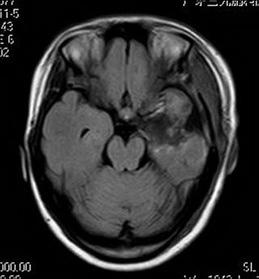

经神经外六科吴杰主任及其团队详细评估后,为小敏全麻下行“左前颞叶切除术”。术后,小敏恢复良好,至今未见癫痫发作。术后病理回报提示:1、(左前颞叶、左海马)形态结合免疫组化符合局灶皮层发育不良伴海马硬化;2、(左杏仁核)符合癫痫改变。

术后MR